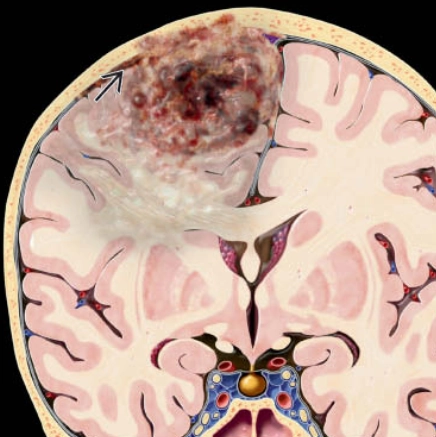

U nguyên bào thần kinh đệm (Glioblastoma- GBM)